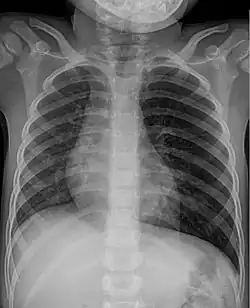

Knochensplitter oder Fischgräten können nach dem Verschlucken in die Schleimhaut des Schlunds oder der Speiseröhre eingespießt werden und dort zu Entzündungen führen. Verschluckte Fremdkörper, die in den Magen gelangt sind, gehen je nach Größe meist auf natürlichem Wege wieder ab. Bezoare (Trichobezoare, etwa eigene Haargeschwülste beim Menschen, und bei Tieren aus Pflanzenfasern gebildete Phytobezoare) können als Fremdkörper die Magen-Darm-Passage behindern.[1] Bei Knopfzellen wird die Entfernung aus dem Magen empfohlen, da eine Zerstörung der Hülle durch die Magensäure und ein Freiwerden giftigen Inhalts befürchtet werden muss. Grundsätzlich ist eine Entfernung bis in den oberen Dünndarm mittels Endoskopie möglich.